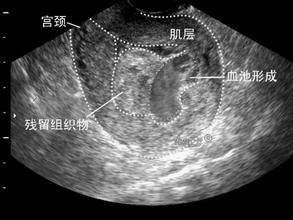

首先,發生不全流產的女性會有長時間出血的症狀,出血時間通常在兩周以上,有的甚至還超過3周;其次,出血量大是不全流產的另一種表現,不全流產的女性出血量通常會大於平時月經量一部分妊娠物已排出,尚有一部分殘留在子宮腔內,或仍附著在子宮壁上,子宮強烈的收縮使患者感到腹部劇痛及腰部酸痛,流血量較多,子宮口未閉。宮頸口已擴張,不斷有血自宮頸口內流出,有時還可見有胎盤或胎兒組織堵塞在擴張的宮頸口內。B超檢察子宮內沒有完美的胚胎外形,沒有心跳,只見血塊和邊界不規則的塊狀物,宮頸口張開,有時見宮頸口內有組織物。如果不完全流產的症狀發生後,持續出血時間長引起貧血,患者有面色蒼白、頭昏等表現,血液檢察可見紅細胞和血紅蛋白減少;出血過多引起休克的,出現心跳加快、出冷汗、少尿、暈厥、甚至昏迷。

不全流產常發生於妊娠8周后.此時胎盤已形成,當胎兒排出後,胎盤部分或全部瀦留在子宮腔內,影響子宮收縮,導致出血不止,甚至發生出血性休克。